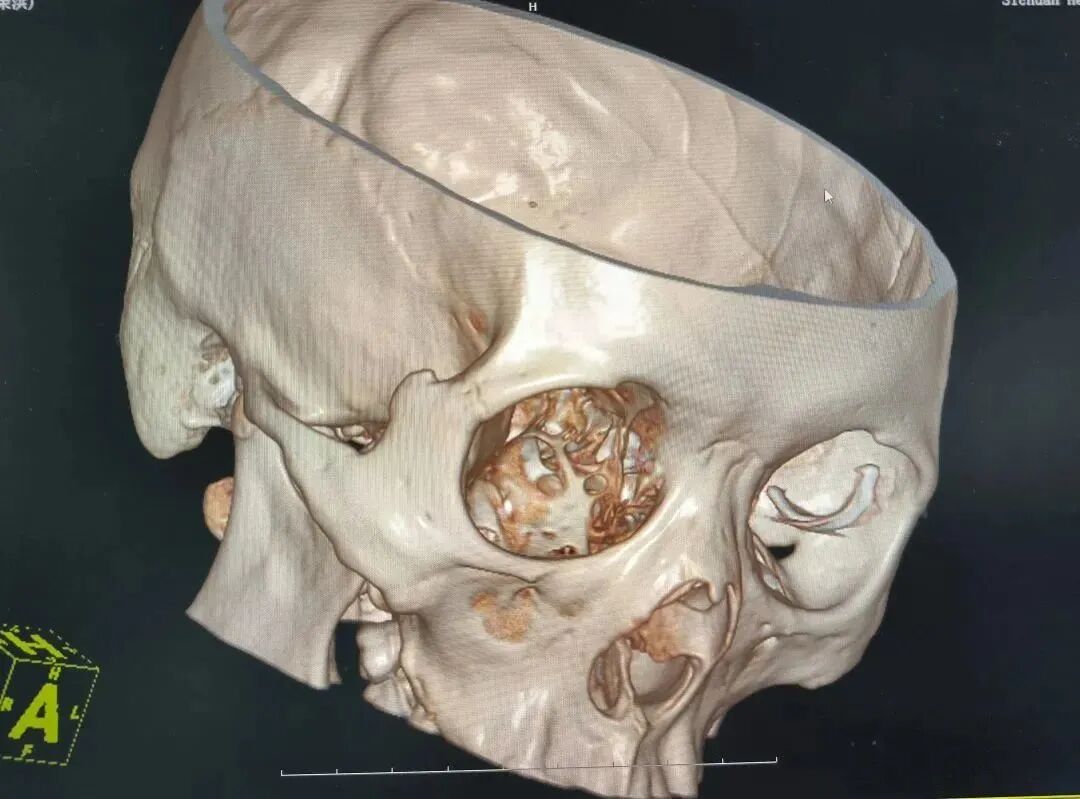

值班医生苏国强第一时间完善眼眶CT及三维重建,初步评估铁钉尚未刺破眼球,但异物较大,三维重建提示异物边缘锐利,贸然取出有造成术中二次损伤的风险。